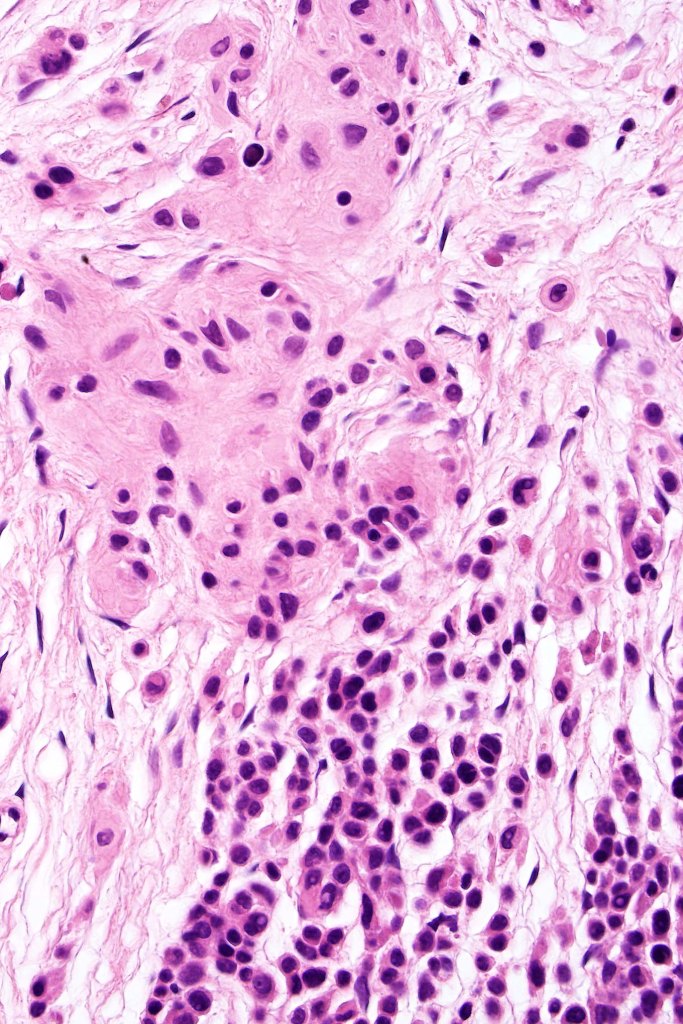

This is uncommon and presents clinically with a history of recent change in color of a common or less often congenital nevus causing concern for melanoma by the clinician. Some, but not all are probably deep penetrating and combined nevus variants. Others may represent follicular type-A cell nests. It is characterized by the presence of deep nest(s) of type -A nevus cells surrounded by & with overlying type-B nevus cells.